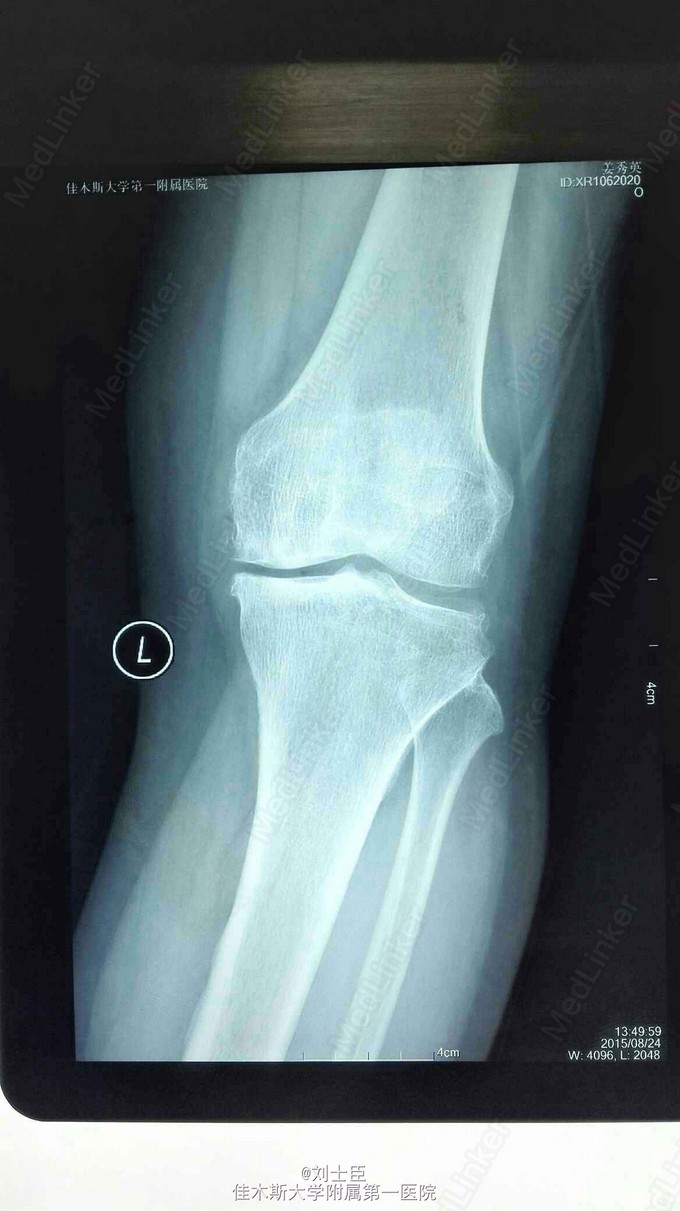

xx,女,54岁。左膝疼痛伴活动受限5年加重1个月。上下楼困难,走平路500米跛行。

左膝内侧压痛明显,伸直10度,屈曲100度。蹲起困难。过伸过曲实验阳性。

左膝关节骨性关节炎。 膝关节镜清理术加腓骨截骨术。

病人术后疼痛减轻,行走自如。蹲起良好。伸直5度,屈曲120度。平路和上下楼疼痛减轻。 术后4周膝关节轻度肿胀。症状体征进一步好转。能长时间行走,间断上下楼。 您对此种做法的观点?同意或不同意。 您对此病的治疗观点?您通过自己的治疗方法,患者的满意率如何? 您是否会选择膝关节置换?您有把握让假体生存20年或更长,而患者满意吗?